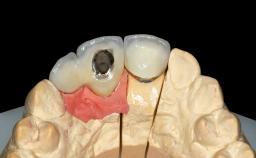

Replacement of Four Incisors with a Fixed Partial Denture on Two Narrow-Neck Implants after Implant Failure

| Prosthesis Type | FDP |

| Retention | Screw-retained, with splinted implants Screw-retained, with splinted implants |

| Provisional Implant-Supported Prosthesis | Prosthodontic margin >3 mm apical to mucosal crest Prosthodontic margin >3 mm apical to mucosal crest |